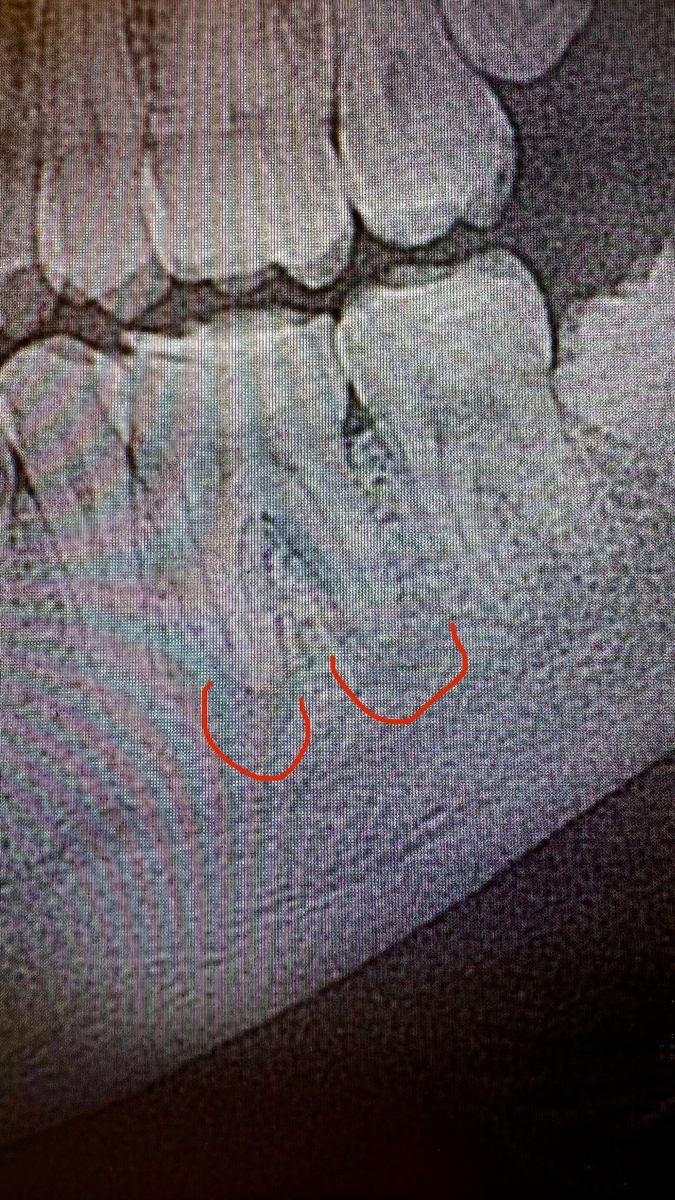

Лечила молодого человека в 2019 году, был свищ на десне возле зуба. Снимки, конечно, не очень хорошего качества, но видно какие были «кисты» на корнях зуба. Специально продублировала снимок и выделила зону воспаления в кости вокруг корня красным цветом.